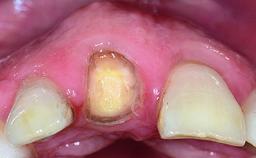

A 36-year-old male patient with a compromised maxillary central incisor was referred by his general dentist for consultation. The patient’s chief complaints were the gradual debonding of a temporary crown on the right central incisor and unsatisfactory esthetics due to an increasing diastema between the right central and lateral incisors. The patient reported a traumatic event some years previously, when a crown had been placed after root-canal treatment. The referring dentist wanted to provide a new crown restoration, but was concerned about the condition of the residual root. Anamnesis was negative for any other dental or periodontal pathology in the remaining dentition. The patient reported taking no medications: He was a smoker (10 to 15 cigs/day) and had realistic esthetic expectations.

Abutment Type CAD/CAM

Provisional Implant-Supported Prosthesis Prosthodontic margin > 3 mm apical to mucosal margin Prosthodontic margin > 3 mm apical to mucosal margin